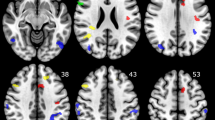

Recent evidence suggests that anterior cingulate cortex (ACC) maturation during adolescence contributes to or underlies the development of major depressive disorder (MDD) during this sensitive period. The ACC is a structure that sits at the intersection of several task-positive networks (eg, central executive network, CEN), which are still developing during adolescence. While recent work using seed-based approaches indicate that depressed adolescents show limited task-evoked vs resting-state connectivity (termed ‘inflexibility’) between the ACC and task-negative networks, no study has used network-based approaches to investigate inflexibility of the ACC in task-positive networks to understand adolescent MDD. Here, we used graph theory to compare flexibility of network-level topology in eight subregions of the ACC (spanning three task-positive networks) in 42 unmedicated adolescents with MDD and 53 well-matched healthy controls. All participants underwent fMRI scanning during resting state and a response inhibition task that robustly engages task-positive networks. Relative to controls, depressed adolescents were characterized by inflexibility in local efficiency of a key ACC node in the CEN: right dorsal anterior cingulate cortex/medial frontal gyrus (R dACC/MFG). Furthermore, individual differences in flexibility of local efficiency of R dACC/MFG significantly predicted inhibition performance, consistent with current literature demonstrating that flexible network organization affords successful cognitive control. Finally, reduced local efficiency of dACC/MFG during the task was significantly associated with an earlier age of depression onset, consistent with prior work suggesting that MDD may alter functional network development. Our results support a neurodevelopmental hypothesis of MDD wherein dysfunctional self-regulation is potentially reflected by altered ACC maturation.